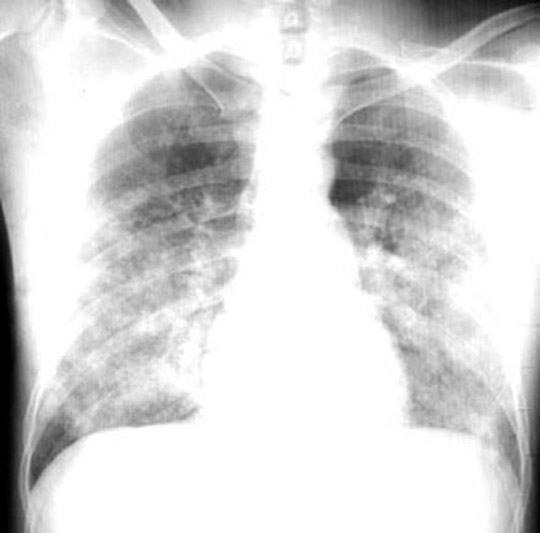

Findings:

• Bilateral alveolar densities

• Butterfly pattern

• Hilar haze

Diagnosis

Pulmonary Edema